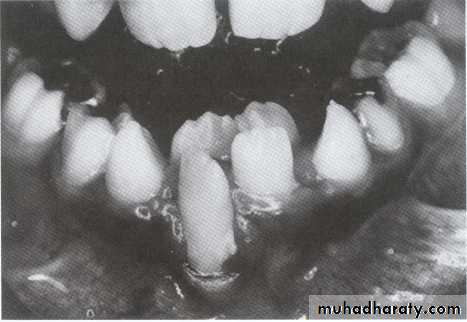

COLLEGE OF DENTISTRYEnvironmental crowding associated with:

1- Trauma like facial burn.UNIVERSITY OF MOSUL

COLLEGE OF DENTISTRY• 2- Discrepancy in size of individual teeth.

• 3- Rotate maxillary incisor with enlarge cingulum.• Environmental crowding associated with:

• 4- Iatrogenic treatment.

• 5- Transposed teeth.• 6- Uneven resorption of deciduous roots.

• 7- Prolonged retention of primary teeth.

• 8- interproximal caries if not restored.

• 9- Abnormal exfoliation sequence.

• 10- Altered eruption sequence.